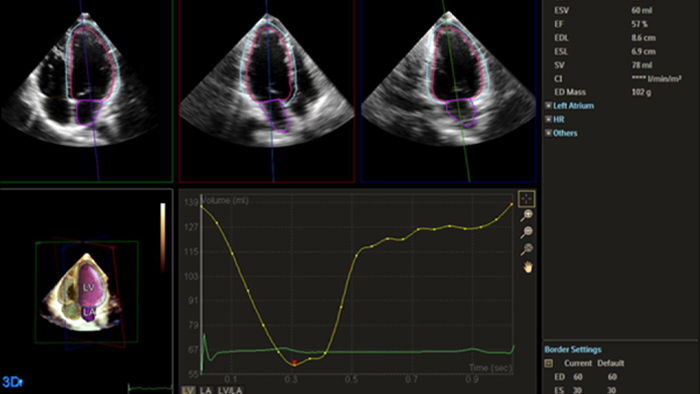

La ecocardiografía suele ser la primera prueba de imágenes cardiacas que se realiza en pacientes con sospecha de insuficiencia cardiaca. Un ecocardiograma nos proporciona una gran cantidad de información sobre la estructura y la función cardiaca utilizando tanto las herramientas 2D como las 3D. En muchas situaciones, la ecocardiografía puede ayudarnos a comprender la etiología de la insuficiencia cardiaca. Uso rutinariamente la información derivada tanto del análisis como de la deformación 2D y 3D para entender mejor a mis pacientes. AutoStrain, Dynamic HeartModel y Auto RV son herramientas valiosas que se utilizan tanto en el diagnóstico como en el control de pacientes con insuficiencia cardiaca.”

Las herramientas de adquisición de imágenes sólidas y reproducibles son importantes para diagnosticar y controlar la progresión de la enfermedad en la insuficiencia cardiaca. Las directrices actuales apoyan el uso de herramientas avanzadas de ecocardiografía, como la evaluación 3D y la deformación longitudinal de los volúmenes y funciones del VI y el VD.

Automatización para una cuantificación cardiaca reproducible sólida y probada tanto en 2D como en 3D.

Cuantificación mediante Dynamic HeartModel.